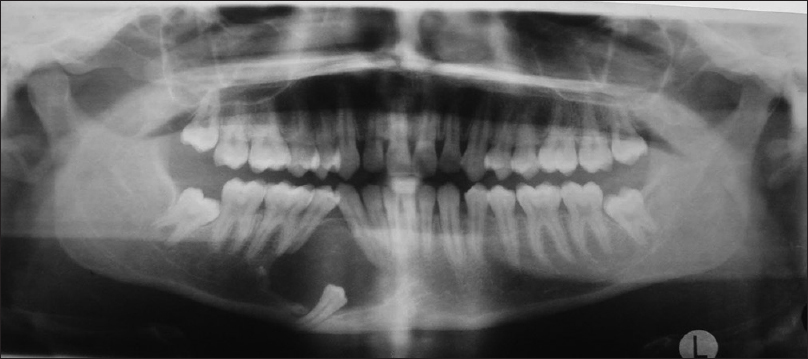

Background: The purpose of the study was to correlate the provisional diagnosis of pericoronal radiolucencies associated with impacted, embedded, or unerupted teeth with the histopathologic diagnosis, and also to emphasize the importance of early detection for better diagnosis and management.

Methods: This is a retrospective study involving 18 cases of pericoronal radiolucencies associated with unerupted, embedded, or impacted teeth whose data during 1-year period were retrieved, and were reviewed for clinical, radiological, and histopathologic data. Also, comparison and correlation of clinico-histopathologic diagnosis was made.

Results: Of the 18 cases, 11 were provisionally diagnosed as dentigerous cyst and the remaining were diagnosed as ameloblastoma, odontogenic keratocyst, adenomatoid odontogenic tumor, and calcifying epithelial odontogenic cyst. Histopathologic diagnosis of the 18 cases showed varied results, with only 10% correlating with the provisional diagnosis.

Conclusion: Although many pathological processes may present radiographically as pericoronal radiolucencies associated with unerupted teeth, the most common is the dentigerous cyst. Hence, it is crucial for the clinician to fully investigate all teeth that fail to erupt at the expected time, and promptly initiate appropriate assessment and management of suspected cystic lesions.